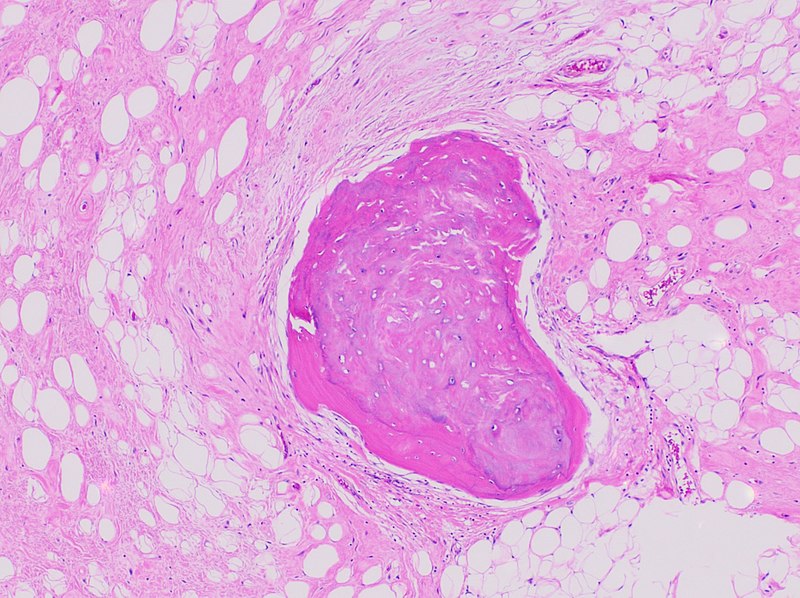

Rhabdomyoma

Rhabdomyomas are benign tumors composed of skeletal muscle.

Rhabdomyomas can develop in heart muscle, termed cardiac rhabdomyomas, which are associated with tuberous sclerosis.

Although rhabdomyomas are uncommon in general, they are the most frequent kind of cardiac tumor among infants and young children.